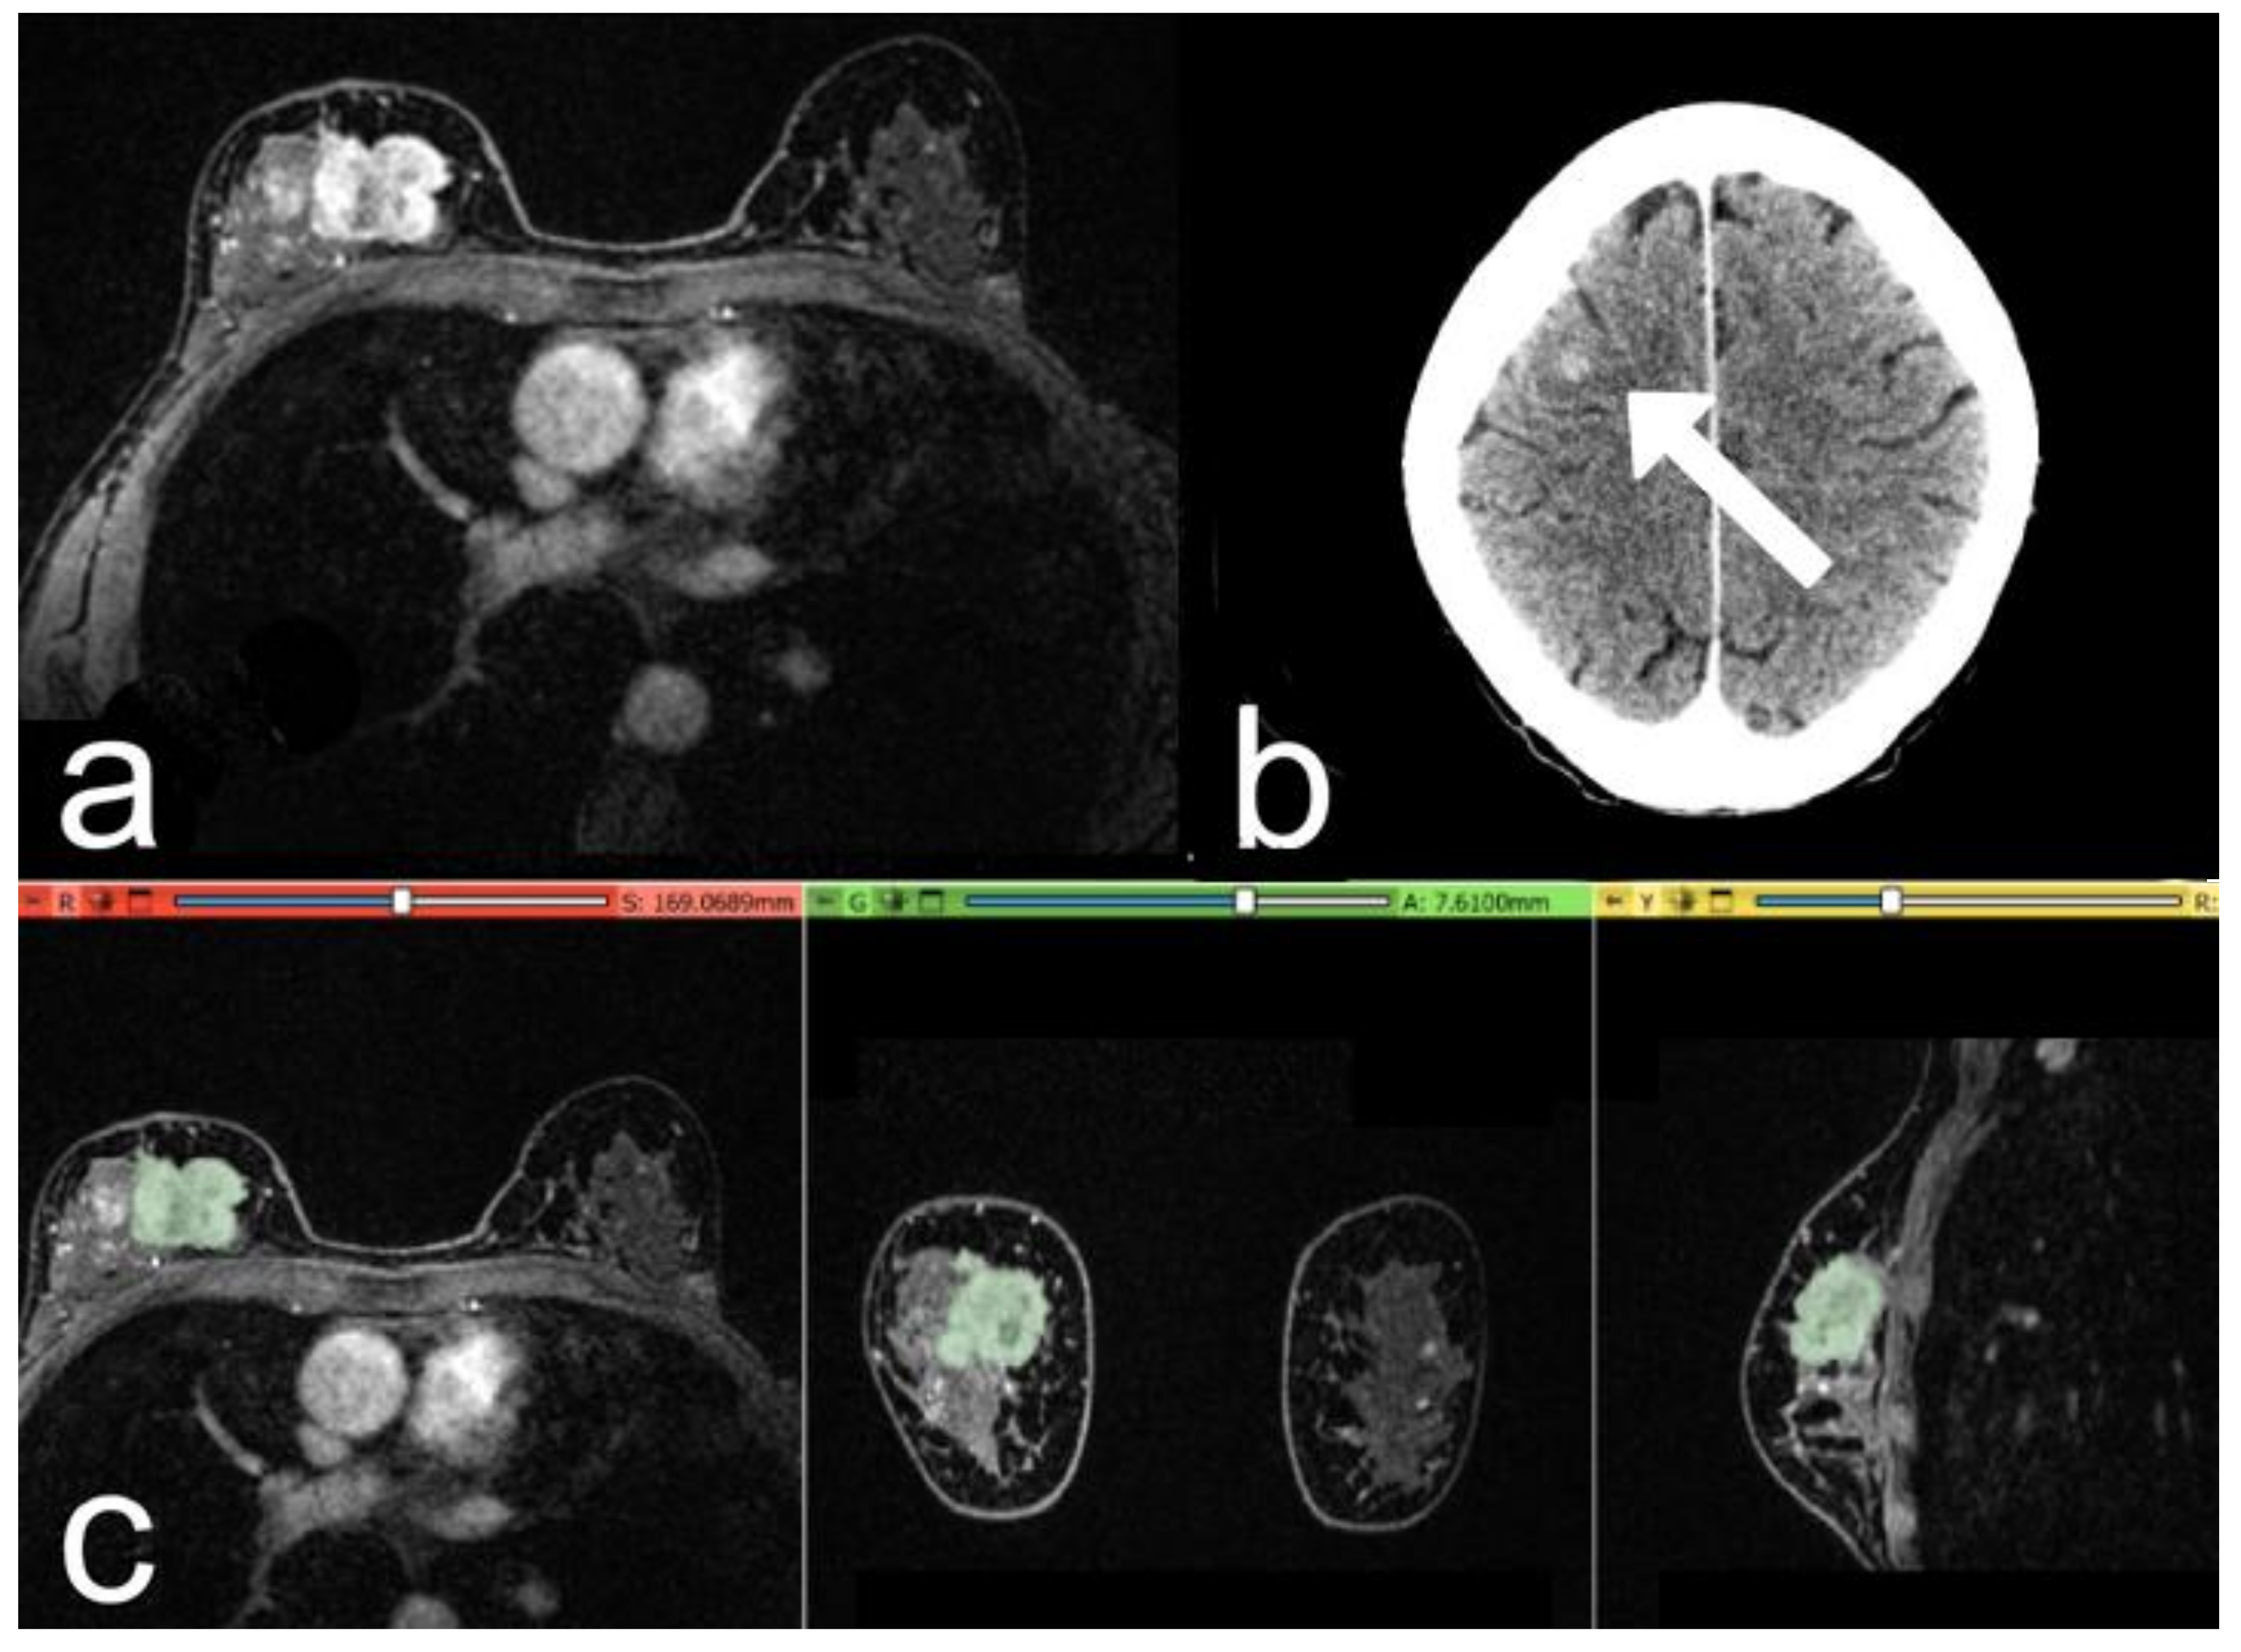

2.4. Segmentation and Pre-Processing

2.5. Volumes Extraction

2.6. Metastasis Prevision Assessment

3. Results